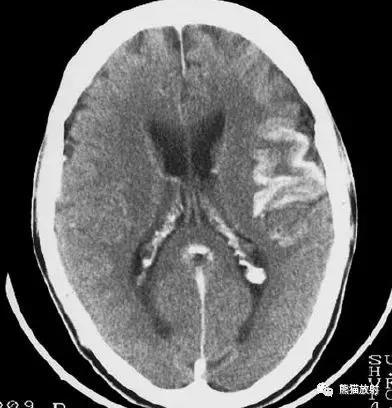

右侧豆状核梗死灶(发病后15d),明显均匀强化。另左侧丘脑见腔隙性梗死灶。

左侧大脑中动脉区域大面积梗死,明显不均质强化。

右侧大脑中动脉区域脑梗死,脑回样强化。

左侧额叶脑梗死(发病后12d),由于模糊效应平扫显示不清,增强扫描脑回样强化。

右侧基底节区脑梗死,增强后病灶看上去有所缩小。